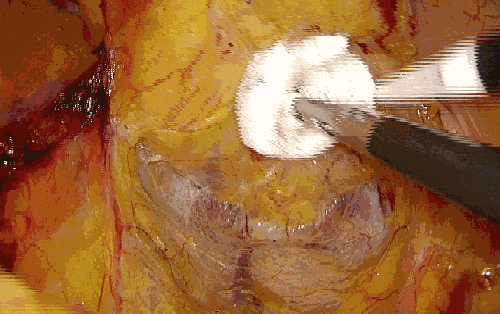

五、辅助分离作用

利用纱布辅助在正确的解剖间隙内进行钝性分离,也是不错的选择。